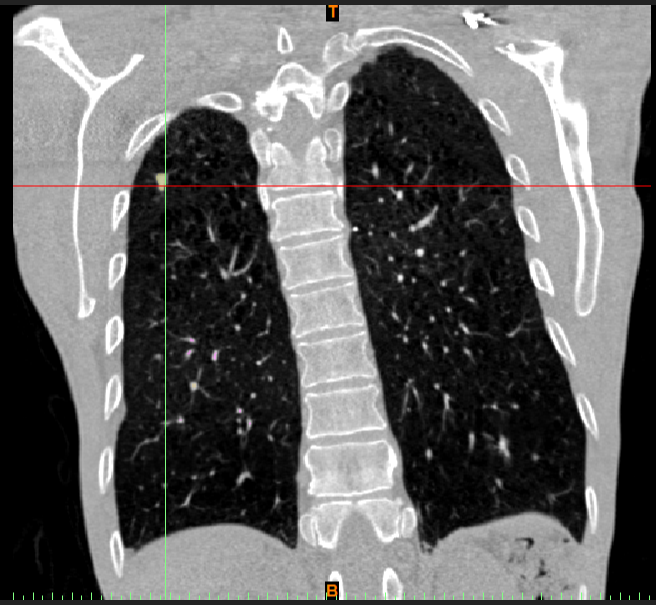

CT冠状位

随着我国城市化进程的加快,大气污染近期难以得到有效控制,预计近几年内我国肺癌发病率仍呈上升趋势。据统计,肺癌患者的疾病谱较20年前有很大变化,腺癌成为最常见的类型。随着CT筛查的普及,越来越多的肺部小结节被检查出,这些结节可能代表着良性结节,也可能代表着癌前病变、原位癌或者微浸润腺癌、浸润性腺癌。

早期腺癌(非浸润性腺癌或者微浸润腺癌)在CT的表现一般为毛玻璃样结节,通过手术治疗,其5年期无疾病生存期分别为100%或接近100%,基本可以达到治愈的目的。目前对于此类病灶的手术治疗方式主要为肺叶切除术、楔形切除术以及肺段切除术。越来越多的研究资料提示:楔形切除、肺段切除与肺叶切除有相似的临床效果。

肺叶切除要切除病灶所在的整叶肺组织,而毛玻璃样结节直径通常为1-2cm,对于周围型的肺结节,肺叶切除显然造成了过多的肺组织损失,对于患者肺功能影响较大。